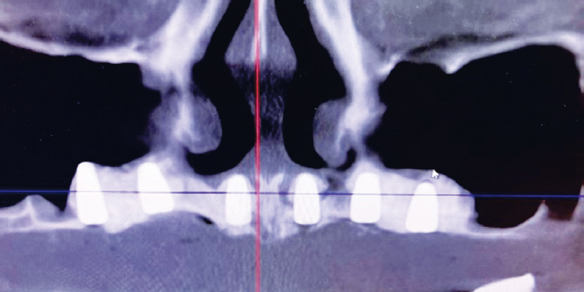

Рис. 3. Компьютерная томограмма верхней челюсти после проведения увеличения объема костной ткани в области гайморовых пазух и дна полости носа

Fig. 3. Computed tomography of the upper jaw after bone augmentation in the maxillary sinuses and floor of the nasal cavity

Через полгода после синус- и назалифтинга пациентке проведено планирование (рис. 4) и установка дентальных имплантатов (рис. 5).